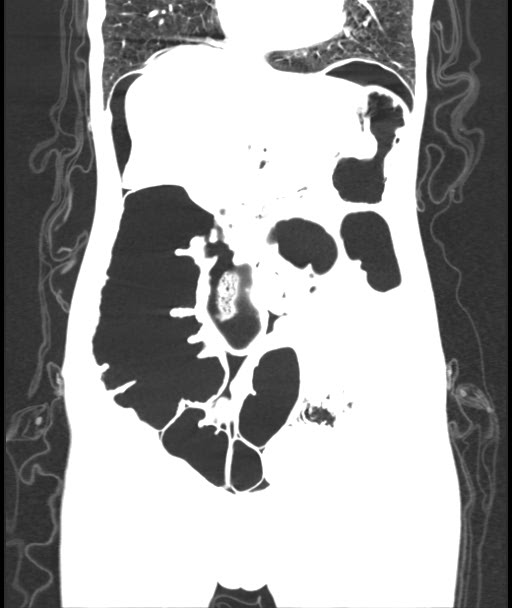

CECT Abdomen: F/S/O Acute Intestinal Obstruction (transition point in transverse colon) with minimal free fluid in pelvis with pneumoperitonium with few air foci in the wall of ascending colon Pneumatosis intestinalis

Cause Midgut volvulus

Adhesion Band

Figure 2: Cect Showing Features of Intestinal Obstruction

Radiologic imaging may be abnormal and detect CV in 45–56% of the cases [5] .Plain abdominal x-ray is highly sensitive for the diagnosis of CV with the characteristic “coffee bean“ sign deformity, its apex pointing to the left upper quadrant [9]. Other findings commonly seen are cecal dilatation (98−100%), single air–fluid level (72–88%), small bowel dilatation (42–55%), and absence of gas in the distal colon (82%). CT is more sensitive and specific for diagnosing CV and detecting complications [10].